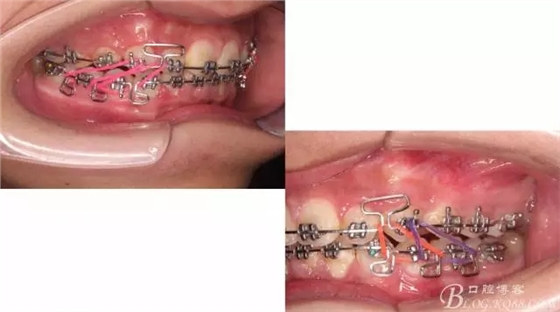

接下來盡管配合些雙側(cè)后牙對(duì)角牽引,咬合關(guān)系依,不盡人意。

下頜配合多曲方絲,三角牽引,調(diào)整咬合。

中線不齊,咋辦?繼續(xù)哄哄患者配合,2牽+斜牽。

努力沒有白費(fèi),中線基本對(duì)齊!